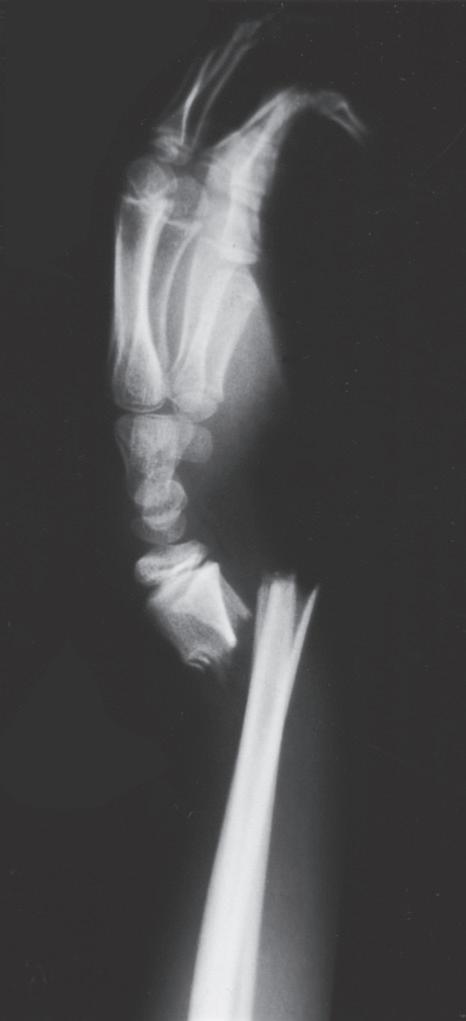

Remodeling may occur readily in the plane of a joint (Fig. 1.5), but it occurs far less readily, if at all, in children with rotational deformity or angular deformity not in the plane of the joint.14,65,66,69 Abraham67 studied the remodeling potential of immature monkeys and found that remodeling occurred at the growth plate and along the concavity of the shaft deformity, with minimal resorption on the convexity of the shaft. Diaphyseal remodeling and physeal reorientation with growth contributed similar amounts to the degree of remodeling. In femoral shaft fractures in children, 75% of the remodeling of angular deformities takes place in the physis, and 25% comes from appositional remodeling of the diaphysis.70 The physis adjacent to a fracture realigns itself with asymmetric growth to become perpendicular to the forces acting through the bone, and most authors believe this is the primary mechanism for remodeling.66

Significant angulation in the midportion of long bones is not usually acceptable and does not remodel very well, depending on the age of the child. In children younger than 8 years, residual angulation is more acceptable. If the angulation is less than 30 degrees and is within the plane of the joint, remodeling toward normal alignment can be expected.2,19 The potential for remodeling to an acceptable functional and cosmetic outcome depends on many factors, including which bone is fractured, how close the fracture is to a joint, the orientation to the joint axis, and the amount of growth remaining for the child.66 Side-to-side (bayonet or

Fig. 1.4 Anteroposterior of a 9-yearold with a distal radius fracture that was pinned in poor position (A), now 4 weeks out from pinning (x-ray after pin removal). Anteroposterior of the same distal radius fracture (B) at 12 months from the injury with complete remodeling. Anteroposterior of a proximal humerus fracture in an 11-year-old at the time of injury (C) and at 6 months (D). Similar to the distal radius, these anatomic locations have tremendous remodeling potential secondary to the large contribution of growth from adjacent physes.

Fig. 1.5 (A) Radiograph of the distal portion of the radius in an 11-year-old girl at the time of cast removal 6 weeks after injury. (B) A lateral radiograph taken 3 months later shows considerable remodeling of the fracture in the plane of the joint.

Fig. 1.6 Radiograph of a femoral shaft fracture in a 2-yearold boy in a spica cast at the time of injury (A) and at 12 months postinjury (B). The fracture demonstrates bayonet apposition with otherwise good alignment. The bayonet apposition remodeled within 12 months in this young child.